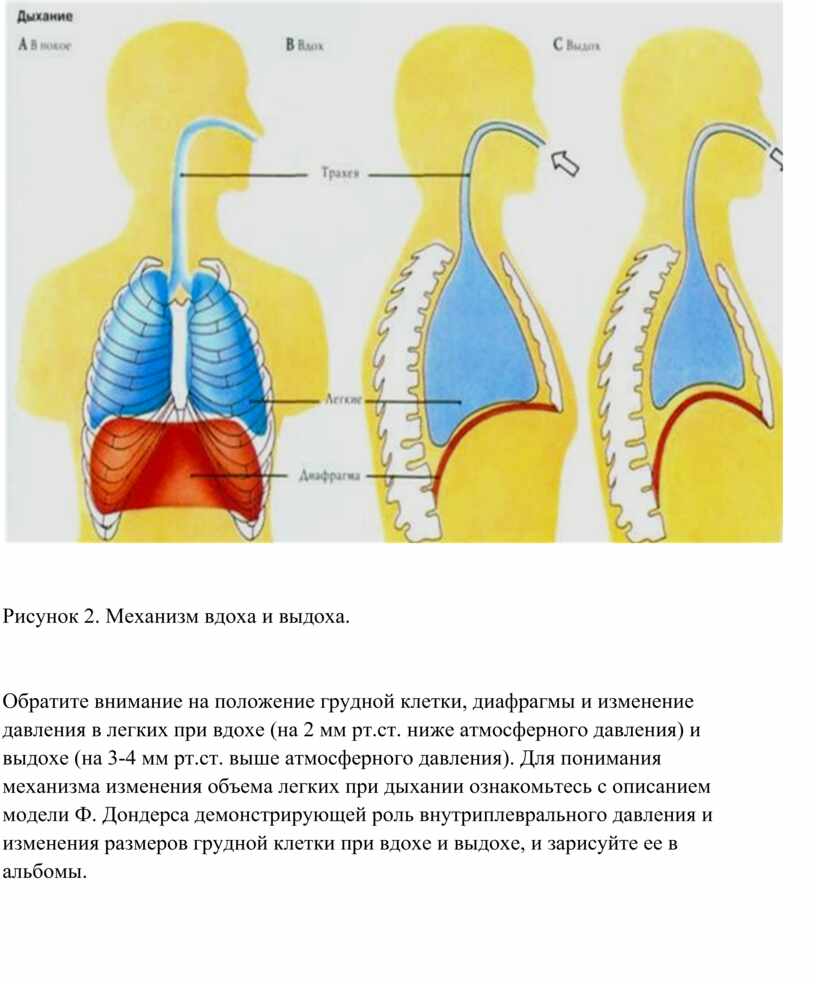

При любом типе дыхания за обработку кислорода отвечают легкие. Но их увеличение, как и изменение объема полости груди, зависит от 2 разных способов:

- При вдохе стенка груди приподнимается и отодвигается от позвоночника, из-за чего полость грудной клетки спереди увеличивается (образуется дополнительный объем между позвоночником и грудиной). В этом процессе участвуют ребра, прикрепленные к позвоночнику под острым углом. Своими концами они формируют дугу, расширяя возможный объем. Так как ребра крепятся к грудной кости, они тянут ее за собой.

- Второй способ зависит от опущения грудобрюшной преграды по направлению книзу. Это – диафрагма, имеющая куполообразную форму. Грудные мышцы отвечают в процессе дыхания за то, чтобы этот купол тянулся вниз, освобождая простор для легких. Середина опускается книзу и создается нужный объем. Из-за опущения грудная часть диафрагмы давит на живот, в результате выпячивается его стенка.

Главный орган в брюшном дыхании — диафрагма. Диафрагмальная мышца — это куполообразная перегородка, она отделяет грудную клетку от органов, расположенных ниже в брюшной полости. На вдохе диафрагмальная мышца идёт вниз и сжимается, заставляя брюшную стенку выдвигаться вперёд. В момент выдоха диафрагмальная мышца возвращается вверх и приобретает форму купола, выгоняя воздух из лёгких.